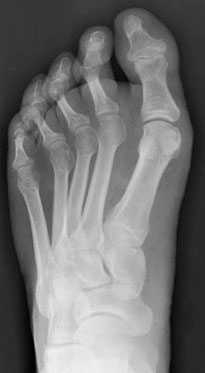

При первом вашем визите в клинику вам будет выполнена рентгенография стоп. Она поможет подтвердить диагноз, оценить тяжесть деформации и при необходимости спланировать хирургическое вмешательство.

Добавочная ладьевидная кость классифицируется в соответствии с рентгенологическими ее особенностями:

- Сесамовидная косточка в толще сухожилия задней большеберцовой мышцы в области его прикрепления к ладьевидной кости

- Добавочная ладьевидная кость, сочленяющаяся синхондрозом с ладьевидной костью

- Костный выступ ладьевидной кости

Рентгенограмма стопы при 1 типе добавочной ладьевидной кости

Рентгенограммы стоп: 3 тип добавочной ладьевидной кости